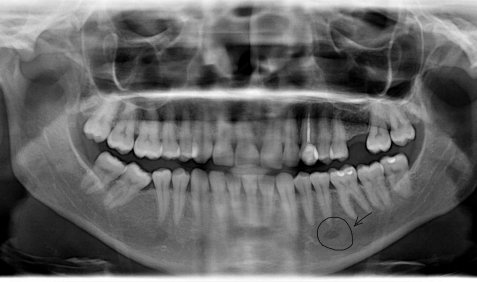

Здравствуйте! Есть ли у меня киста? Если да, то как срочно нужно делать операцию и как она называется?

Какой зуб вы имеете ввиду? Уточните. 18 и 48 зуб необходимо удалить. Далее расскажу после уточнения.